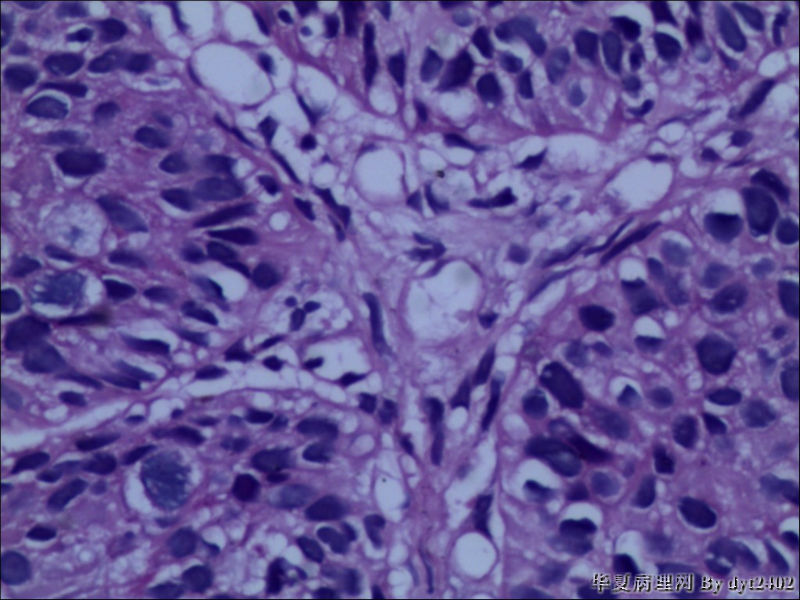

• 宫颈活检 其中一点较迷糊图4

图4

四点中三点是CIN iii,另一点怀疑有更重病变

这个病人是44岁,去年11月底阴道脱落细胞、TCT均见细胞异常,建议活检,病人犹豫,接着单位组织到外院体检时做阴道镜正常,后霉菌感染,此时宫颈未涂醋肉眼看还光滑,直至今年3月来做活检,事前做白带检查又见异常细胞,宫颈未涂醋见后上唇白上皮,涂醋酸后上下唇都有厚白上皮,镶嵌,夹活时上皮剥脱,未能夹到间质,阴道镜医生说至少有CIN III 到原位癌了。。镜下其中3点CIN III无疑,唯有9点处如6、7、11、14等所示结构,但我未见间质浸润,不能说是浸润癌,不知道有没基底细胞样鳞癌的可能,我发了个原位癌不除外深部有更重病变,。